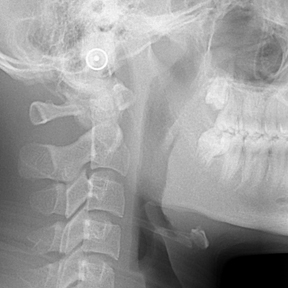

얼굴 골격의 성장에 문제가 있는지를 파악하기 위한 적절한 시기는 초등학교 입학 전인 6-7세경입니다. 이때는 유치에서 영구치로 교환되는 시기로서 부정교합 여부가 결정되는 중요한 시기이므로 이 시기를 잘 관찰하여 부정교합을 예방하는 것 또한 중요합니다. 교정의 정확한 시기는 6개월 간격으로 치과에 정기적으로 내원하여 성장 분석을 받은 후 결정하는 것이 좋습니다.